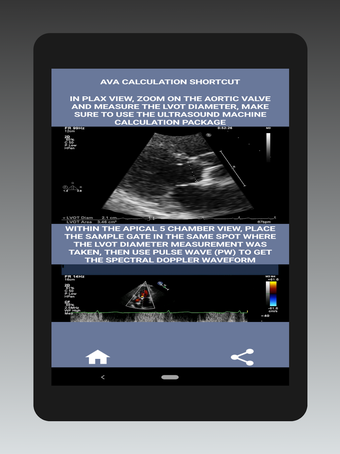

O principal objetivo deste aplicativo é ensinar as pessoas a calcular a área da válvula aórtica. A área da válvula aórtica é o principal fator na determinação da gravidade da estenose aórtica.

A área da válvula aórtica é medida com uma ferramenta usada para medir a distância entre a parede interna da aorta e a parede da o coração.